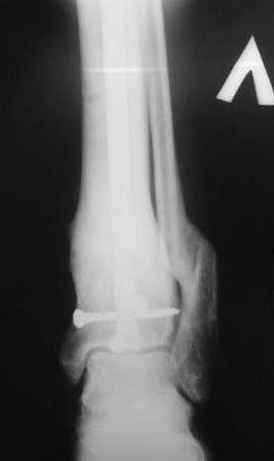

7, 8, 9, 10, 11 - через 8 мес после травмы перелом сросся.